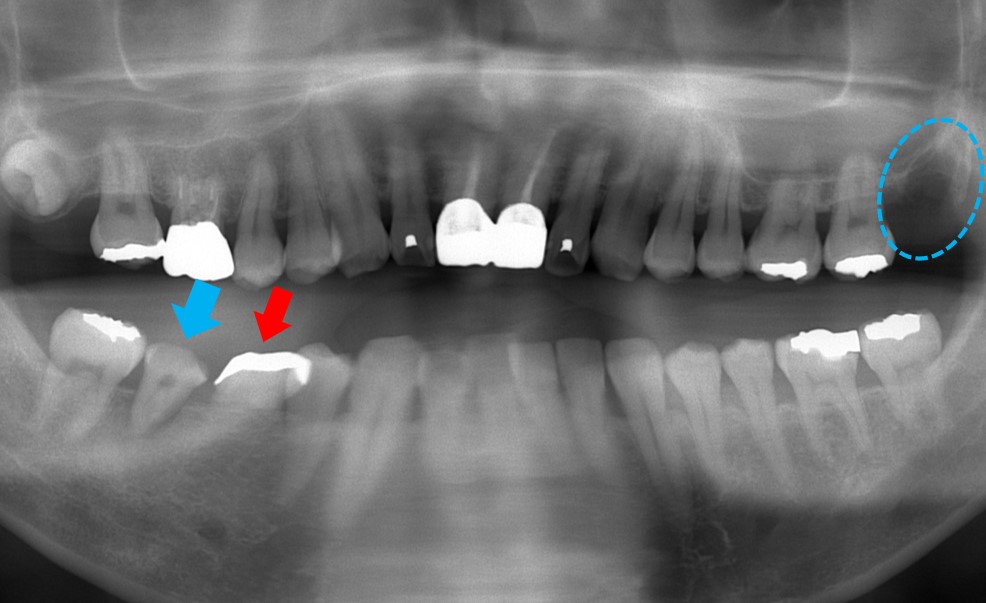

移植した直後です。この場合、歯茎を切開してソケット形成(親知らずが入る部分の骨を削除すること)する必要があります。

抜いた歯の部分に親知らずを移植すれば、骨の削除をする必要がない場合もあるのですが、今回のようにソケット形成する場合は少し大変です。